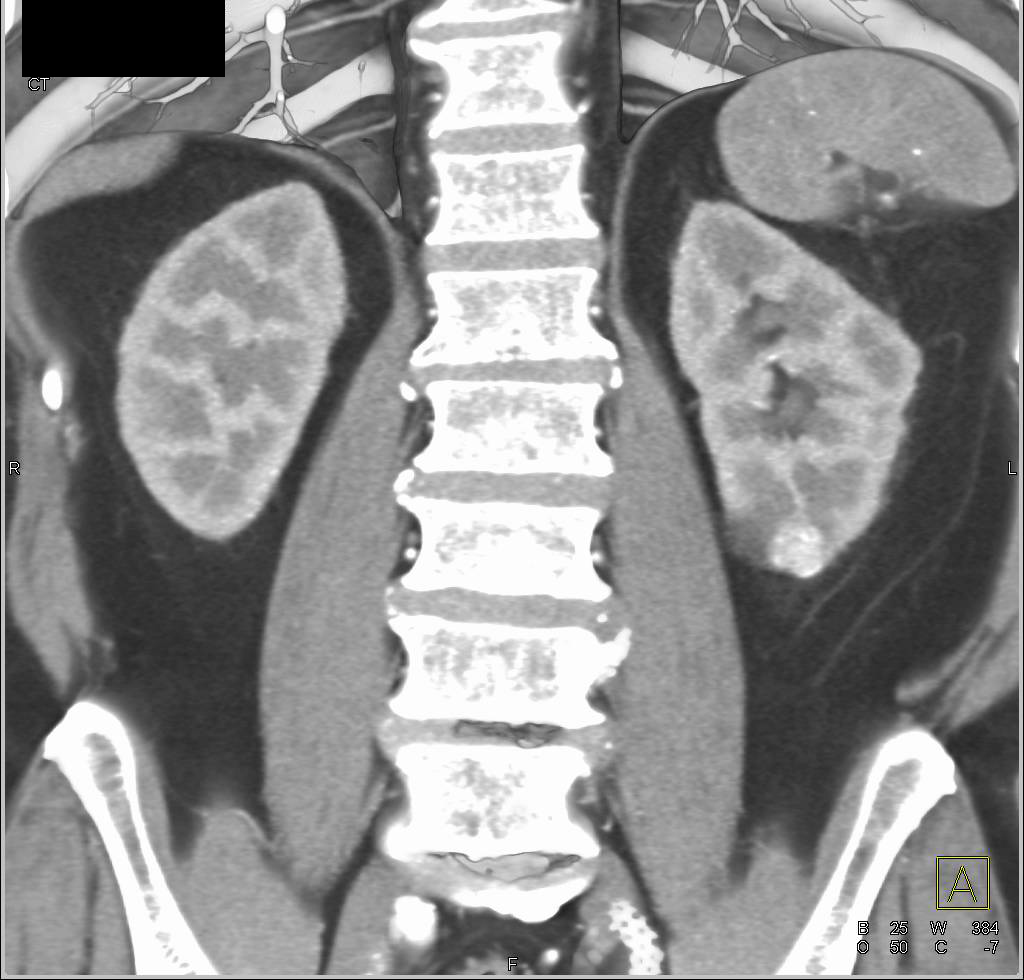

Normal Venous Phase Imaging of the Kidnsys and Adrenals